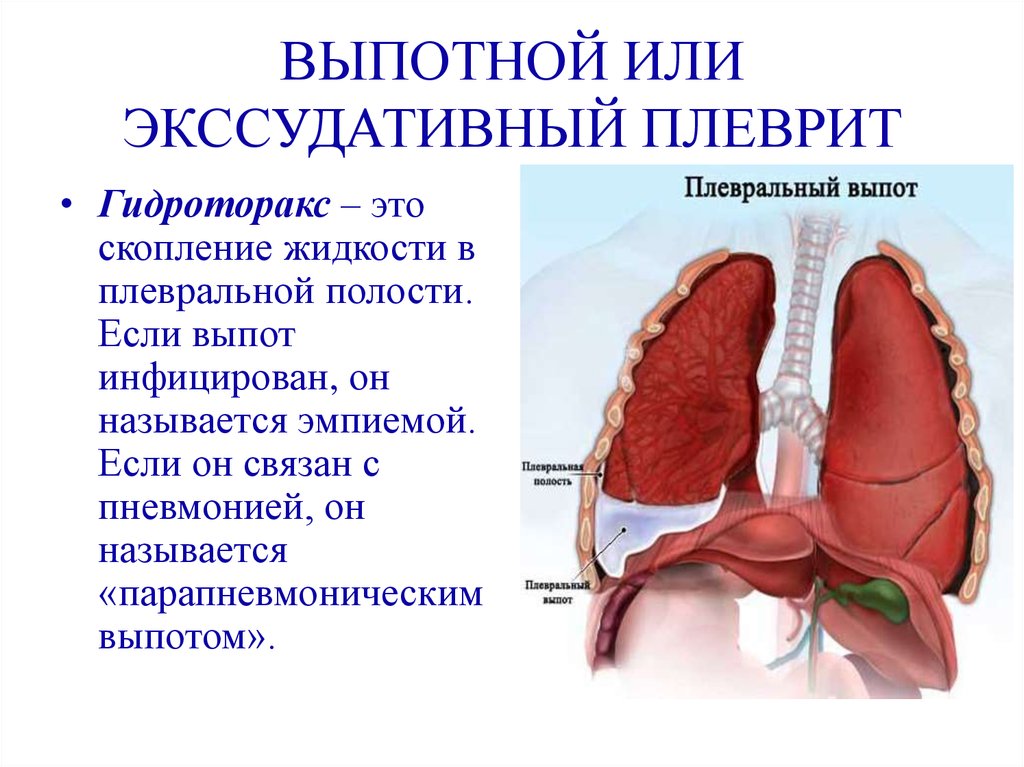

Диагностика плеврального выпота: что нужно знать